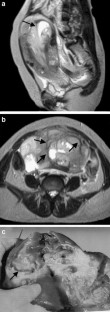

The endometrial cavity may demonstrate various imaging manifestations such as normal, reactive, inflammatory, and benign and malignant neoplasms. We evaluated usual and unusual magnetic resonance imaging (MRI) findings of the uterine endometrial cavity, and described the diagnostic clues to differential diagnoses. Surgically proven pathologies of the uterine endometrial cavity were evaluated retrospectively with pathologic correlation. The pathologies included benign endometrial neoplasms such as endometrial hyperplasia and polyp, malignant endometrial neoplasms such as endometrial carcinoma and carcinosarcoma, endometrial–myometrial neoplasm such as endometrial stromal sarcoma, pregnancy-related lesions in the endometrial cavity such as gestational trophoblastic diseases (hydatidiform mole, invasive mole and choriocarcinoma) and placental polyp, myometrial lesions simulating endometrial lesions such as submucosal leiomyoma and some adenomyosis, endometrial neoplasms simulating myometrial lesions such as adenomyomatous polyp and endometrial lesions arising in the hemicavity of a septate/bicornate uterus, and fluid collections in the uterine cavity (hydro/hemato/pyometra). It is important to recognize various imaging findings in these diseases, in order to make a correct preoperative diagnosis.